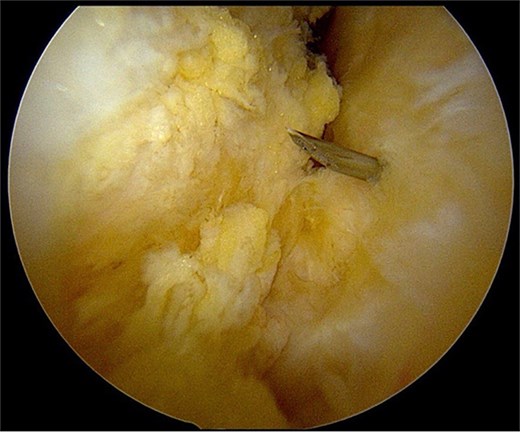

After partial resection of the infrapatellar fat pad for better visualization, the ossicle was exposed by finding the spinal needle and working around it. The fragment was freed arthroscopically using a motorized shaver and a radiofrequency probe (Fig. 5), taking care to protect the patellar tendon.

Once the ossicle was mobile and free (Fig. 6), it was removed either in one piece or was broken into multiple pieces with an arthroscopic burr and then removed with a grasper (Figs 7 and 8). Finally, the tibial tubercle was leveled using either an arthroscopic burr or shaver.

Arthroscopic views of case 1. (A) Ossicle fragment removed. Case 2 (B) tibial tubercle leveling using an arthroscopic Burr. Case 3 (C) ossicle fragment removed.